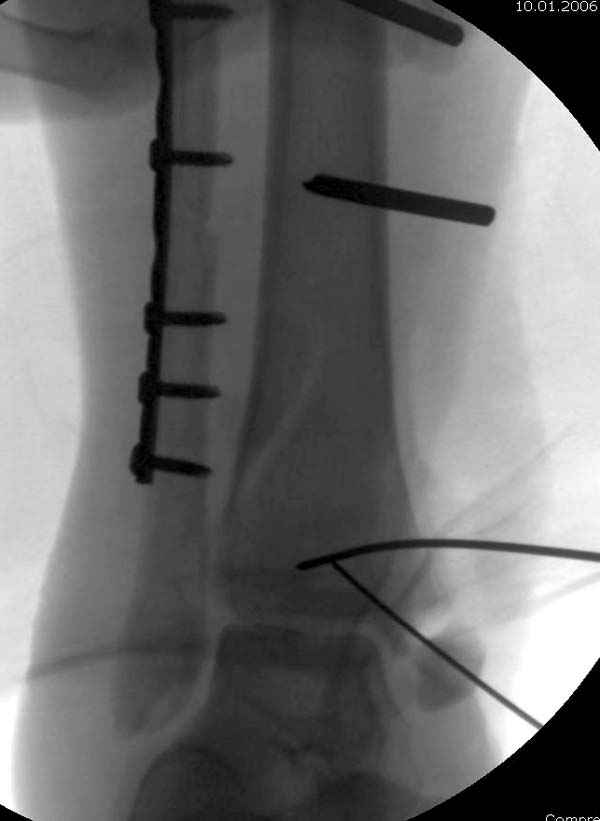

По снимкам довольно сохранный сустав, и такой сустав желательно попытаться восстановить всеми возможными мерами.

Насчет пилона, прошло достаточное время для консолидации и прекрасная возможность для демонстрации, что такие случаи могут быть успешно вылечены остеотомией, несмотря на засторелость.

Из заднего доступа остеотомия тонким остеотомом и коррекции на ЭОПе.

Без применения сложной конструкции, а обычными параллельными шурупами. Шурупы в 3.5 мм и дополнительно фиксация крючковидной пластиной, сделанной из 3.5 mm semitubular пластиной, Butress или аntiglade фиксация.

Здесь алгоритм фиксации свежего перелома и преоперационный план для обсуждаемого случая.